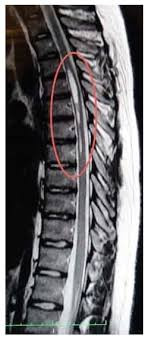

TAG: cedera tulang belakang

Ada 8 Artikel yang mempunyai tag "Cedera Tulang Belakang"